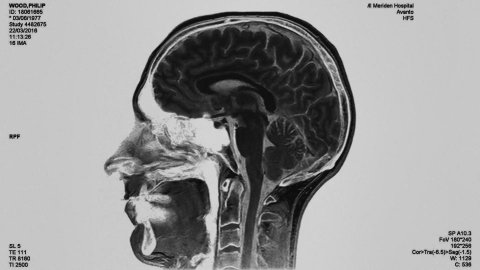

필립우드 소름돋아

필립우드 주소 citizen

ㅓ 2월에도 이야기 했었지만 다시 궁예 찾다가 또 보게됐는데 소름 돋아 ㅠㅠㅠㅠ 시티즌 뭐야